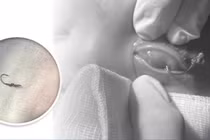

Người bệnh nhập viện trong tình trạng chảy máu nhiều vùng mắt trái, có dị vật kim loại lớn đâm xuyên qua vùng mắt trái, sưng nề, nguy cơ tổn thương sâu đến cấu trúc nhãn cầu.

Ca chấn thương mắt nguy kịch - Ảnh BVCC

Đối mặt với vết thương phức tạp và nguy cơ mất thị lực hoàn toàn, đội ngũ kíp trực Khoa Mắt đã phối hợp khẩn trương với đa chuyên khoa để tiến hành đánh giá lâm sàng, chụp chiếu hình ảnh tổn thương và đưa người bệnh vào phòng phẫu thuật trong thời gian ngắn nhất.

Với sự phối hợp nhịp nhàng, tinh thần khẩn trương và tay nghề vững vàng, các bác sĩ đã thành công loại bỏ dị vật sắc nhọn, đồng thời xử trí triệt để tổn thương phần mềm quanh hốc mắt, bảo tồn tối đa cấu trúc và chức năng nhãn cầu.

Sau phẫu thuật, người bệnh tỉnh táo, không ghi nhận tổn thương xuyên nhãn cầu, thị giác bước đầu được bảo toàn – một kết quả mang lại hy vọng lớn cho quá trình hồi phục tiếp theo.